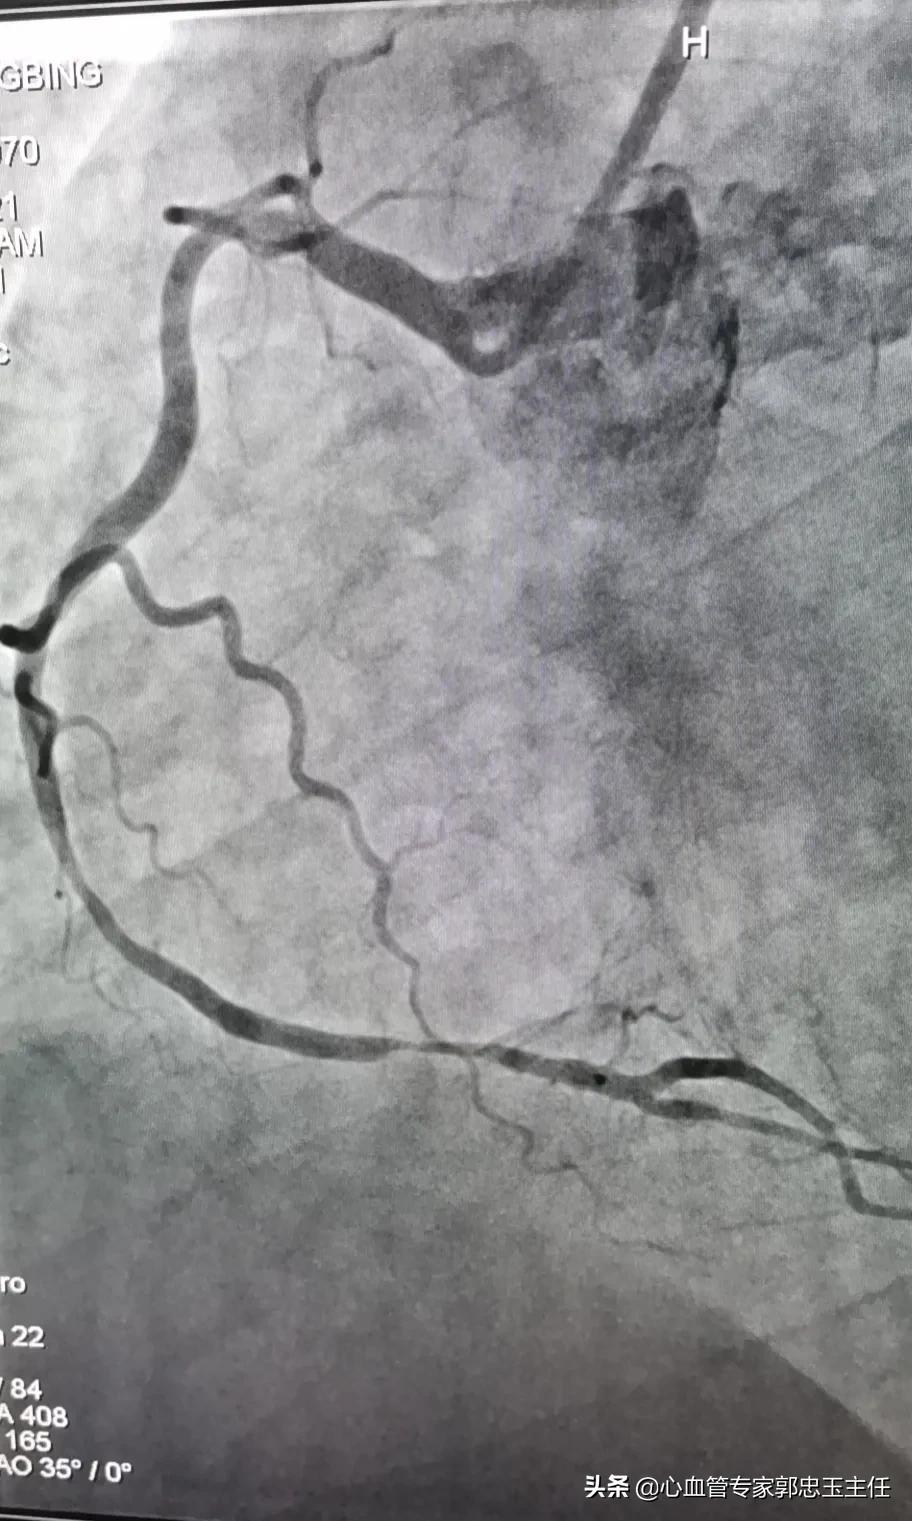

6、冠状动脉造影

冠状动脉造影是通过穿刺外周动脉,选择性地送入造影导管到左右冠脉开口,注射碘造影剂使冠状动脉显影的一种检查技术。是目前诊断 冠状动脉粥样硬化性心脏病 的一种常用而且最有效的方法,是一种较为安全可靠的微创检查手术,已广泛应用于临床,是诊断冠心病的“金标准”。

冠状动脉造影术可以直观地观察冠状动脉血管的走行、数量和有无畸形;评价冠状动脉有无狭窄病变、严重程度、病变长度以及是否存在多支血管病变;评价冠状动脉功能性的改变,包括冠状动脉的痉挛、前向血流、有无侧支循环;左心室造影有助于判断肥厚型心肌病、评估左心功能。

冠脉造影检查更加直观、可靠;经造影检查后可以直接介入治疗,减少造影剂用量和射线暴露;不受心律失常影响。